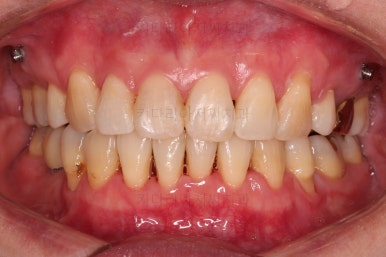

동래임플란트교정 마무리 되었습니다.

임플란트 머리도 잘 올라갔고, 치열도 가지런해졌으며 교합이나 중앙선도 적절히 마무리 되었습니다.

전후 비교를 해보겠습니다.

웃는 모습이 매우 우아해지셨어요.

미소가 굉장히 예뻐지셨습니다.

더군다나 예상한대로 발치교정으로 입을 많이 넣었음에도 팔자주름이나 피부처짐이 없이 잘 마무리 되었습니다.